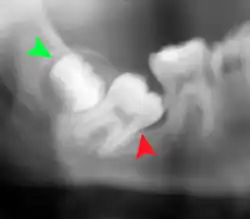

Impacted wisdom teeth are classified by the direction and depth of impaction, the amount of available space for tooth eruption, and the amount of soft tissue or bone (or both) that covers them. The classification structure helps clinicians estimate the risks for impaction, infections and complications associated with wisdom teeth removal.[6] Wisdom teeth are also classified by the presence (or absence) of symptoms and disease.[7]

Impacted wisdom teeth are often described by the direction of their impaction (forward tilting, or mesioangular being the most common), the depth of impaction and the age of the patient as well as other factors such as pre-existing infection or the presence of pathology (cysts, tumors or other disease).[5]: 143–144 Each of these factors is used to predict the difficulty (and rate of complications) when removing an impacted tooth, with age being the most reliable predictor[8] rather than the orientation of the impaction.[9]

Another classification system often taught in U.S. dental schools is known as Pell and Gregory Classification. This system includes a horizontal and vertical component to classify the location of third molars (predominately applicable to lower third molars): the third molar's relationship to the level of the teeth already in the mouth, being the vertical or x-component and to the anterior border of the ramus being the horizontal or y-component.[10]